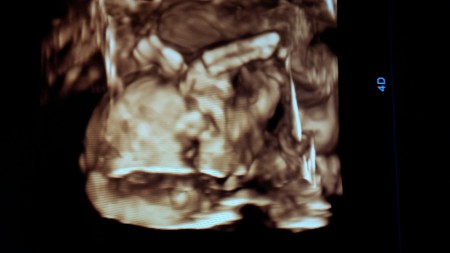

Ultrasonda Bebeğin Saçı Görünür Mü

Ultrasonda Bebeğin Saçı Görünür Mü.